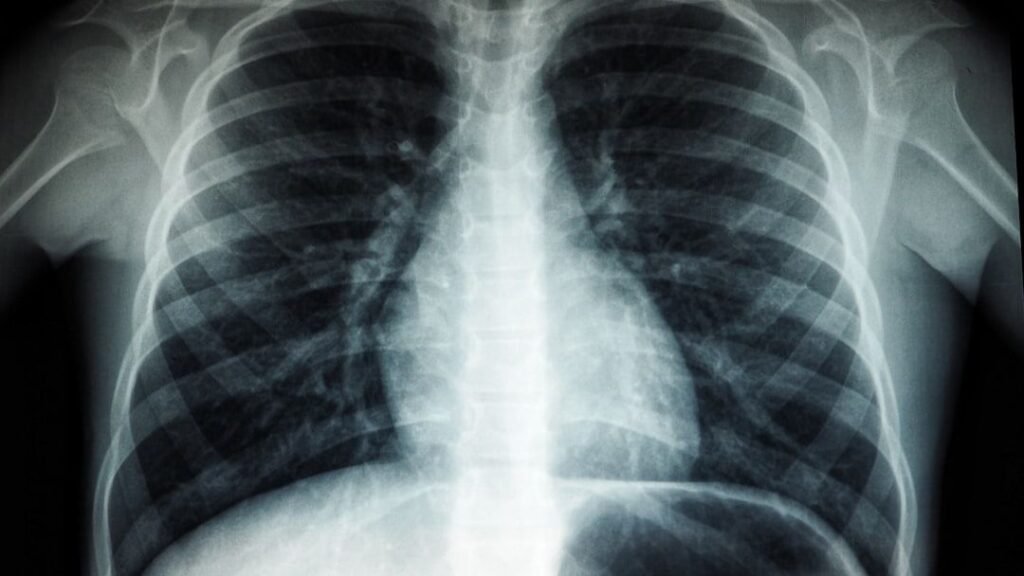

2. X-Rays: A Glowing Screen and Invisible Light

In 1895, Wilhelm Röntgen was studying cathode rays in a darkened lab when he saw something strange: a fluorescent screen across the room started glowing, even though it shouldn’t have. The rays he was working with weren’t supposed to travel through metal or make anything light up from a distance, yet his screen clearly reacted. Most people might have chalked it up to a glitch in the equipment or ignored it as some odd side effect.

Röntgen, however, did the opposite and leaned into the weirdness. He began placing objects between the tube and the screen and noticed their shadows, including the bones inside his own hand, appearing as ghostly shapes. That was the birth of X-rays, a completely new kind of electromagnetic radiation that could pass through soft tissue but not bone or metal. Medical imaging, airport security, and modern diagnostics all trace back to that one eerie glow in a dark room, noticed by someone who refused to dismiss it.